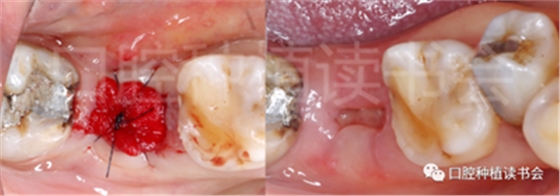

圖1 無法保留的上頜隱裂后牙,拔牙后即刻種植。

(5)可以有效的關閉拔牙創(chuàng)(圖2、圖3)。

圖2 初期穩(wěn)定性良好的位點,采用愈合基臺+縫合固定的方法關閉拔牙創(chuàng),術后1周獲得良好的軟組織愈合。

圖3 初期穩(wěn)定性不足的位點,采用膠原蛋白覆蓋(倍菱)+縫合固定的方法關閉拔牙創(chuàng),術后10天獲得良好的軟組織愈合。